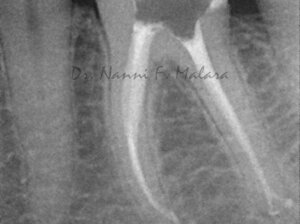

Molare affetto da lesione periapicale a carico di entrambe le radici (Alla radiografia si presentano come aree scure intorno alle radici)

Terapia endodontica con sigillo tridimensionale dei canali radicolari